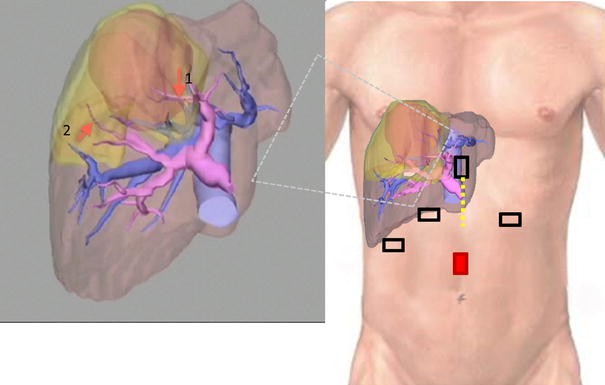

A 68-year-old man with a history of diabetes mellitus and hypertension, but without hepatitis B or C virus infection, was sonographically confirmed to have a large hepatic tumor during follow-up. He had undergone exploratory laparotomy for colon diverticulitis 7 years prior. Abdominal computed tomography revealed a 6.5-cm liver mass, which showed typical HCC features of early arterial enhancement and portal venous washout, located at hepatic segments 4, 5, and 8 and compressing the middle hepatic vein (MHV, Fig. 1A–C). The tumor was supplied by the ventral branches of the right anterior Glissonian pedicle (Fig. 1D). Preoperative evaluation of the liver reserve revealed Child–Pugh class A liver cirrhosis and the 15-min retention rate of indocyanine green (ICG15) was 14 %. The serum levels of tumor markers for alpha-fetoprotein and protein induced by vitamin K absence or antagonist-II were 2.6 ng/ml and 132 mAU/ml, respectively. Preoperative surgical planning using the three-dimensional volume analyzer Synapse Vincent™ (FUJIFILM Co., Japan) suggested the feasibility of limited anatomic subsegmental resection (Fig. 2) instead of central bisegmentectomy (which consisted of 493-ml volume, 46.2 % total liver volume) according to Makuuchi’s criteria [11].

Preoperative surgical planning using 3D liver volumetry and port setting. Calculated volumes of liver (coffee color) and tumor (orange) were 1,067 and 144 ml, respectively. The tumor compressed the MHV and occupied the parenchyma supplied by the S4 Glissonian (arrow 1) and the ventral branch (arrow 2) of the right anterior Glissonian pedicles. The proposed resection area, estimated at 260 ml (24 % total liver volume), is shown in yellow, which covers the tumor completely. Five ports were required for totally laparoscopic left medial and right ventroanterior segmentectomy. The camera port is in red. All ports, except the left subcostal port, were 12 mm in diameter. The portal vein is shown in purple; the hepatic veins and IVC are in blue. Incision for minilaparotomy is shown as the yellow dotted line (Color figure online)